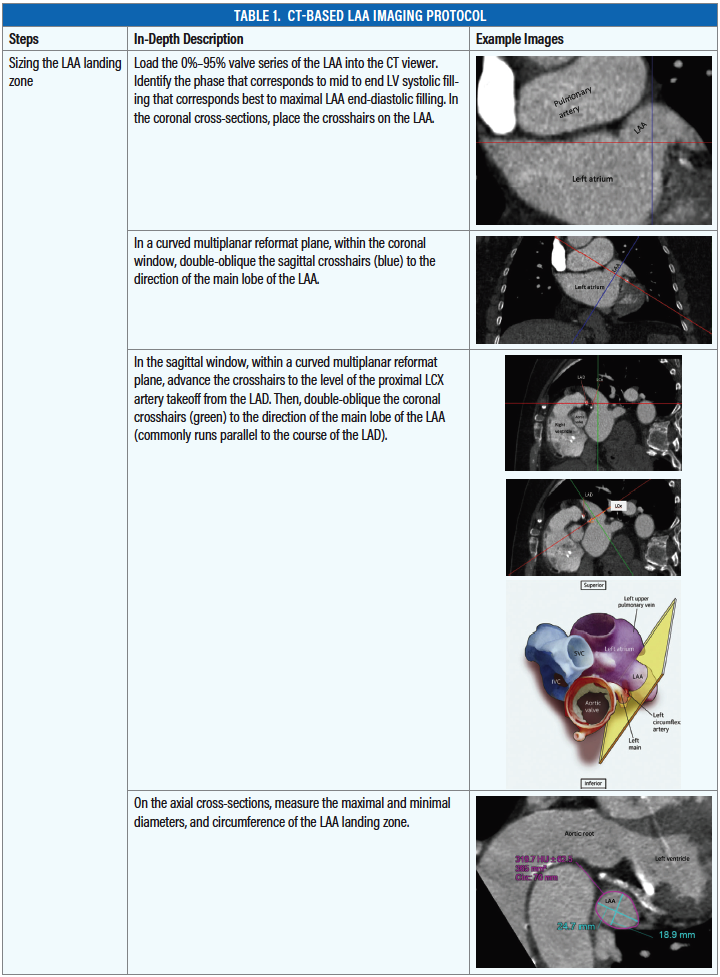

In the search for more comprehensive imaging to provide additional information beyond LAA sizing, CT also has been investigated for evaluating the LAA.9 CT can be performed with cardiac gating with high-resolution scans, providing physicians with excellent image quality and a volumetric, comprehensive data set (Table 1A, Table 1B, and Table 1C). CT has been used to evaluate LAA morphology and the high spatial resolution does perform better than TEE; for instance, CT is more sensitive for detecting postimplantation device leaks.8,10 The promise of a more detailed and comprehensive evaluation of the LAA prompted our center to compare the safety and accuracy of using CT as the primary means for sizing and planning LAA occlusion procedures.

In our pilot study of using CT for LAA occlusion case planning, we learned that CT provides more accurate sizing and improves procedure planning compared to TEE.11 Using CT, we can better measure the appendage, derive coplanar viewing angles, and if available, perform three-dimensional (3D) printing using the CT data (Table 1). Perhaps the most important function is accurate assessment of the morphology and dimensions of the appendage, as CT better appreciates the maximal dimension due to sampling errors made with TEE. Our retrospective series concluded that TEE undersizes the maximal width of the LAA by 2.7 ± 2.2 mm and the length by 4.0 ± 5.8 mm. The ramifications of undersizing are significant; by two-dimensional (2D) TEE maximal width, 62.3% (33/53) of the patients would have received the incorrect initial device and required upsizing to a larger device size intraprocedurally. If not for CT imaging, 12 of 53 patients would have been inappropriately excluded from Watchman implantation either due to width (3/53) or length (9/53) underestimation.11 Multiple device exchanges in the left atrium may increase procedural complications, such as air embolism or catheter-related perforation.